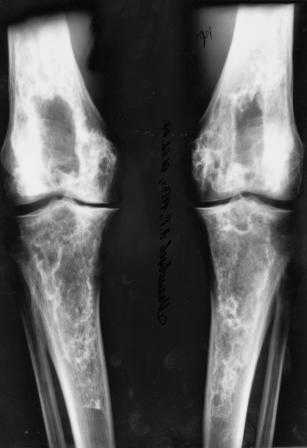

Представленные Вами данные о пациенте 57 дет с болезнью Альбертс-Шенберга чрезвычайно интересны, но диагноз вызывает большие сомнения. Для мраморной болезни характерно прееобладание склероза, а на представленных рентгенограммах преобладает симметричная дезорганизация архитектоники губчатой кости в эпиметафизарной зоне дистальных отделов бедер и голеней.

Уважаемый Константин Иванович! Полностью согласен с проф. Михайловым, данный случай не похож на мраморную болезнь, при которой имеется резкое, строго симметричное и генерализованное уплотнение костной ткани (остеопетроз), и кость оказывается построенной преимущественно из гомогенного компактного костного вещества. Для примера привожу случай из архива нашего института (бедренные, плечевые кости и таз, рис 1,2,3)

Изменения структуры костей у Вашего пациента больше похожи на полиоссальную форму фиброзной дисплазии или болезнь Педжета, возможены также инфаркты костного мозга б.берцовых костей. К сожалению, качество снимка не очень хорошее, непонятно, сохранен ли кортикальный слой б.берцовых костей по передней поверхности.

Не являюсь специалистом по костной патологии, но мне кажется, на ренгенограмме множественные мета-диафизарные образования напоминяющее змееподобных извилистых линии и периостеальные ламинирование очень напоминяет картину остеонекроза (инфаркта) костей, возможно связано с длительным применением стероидов.